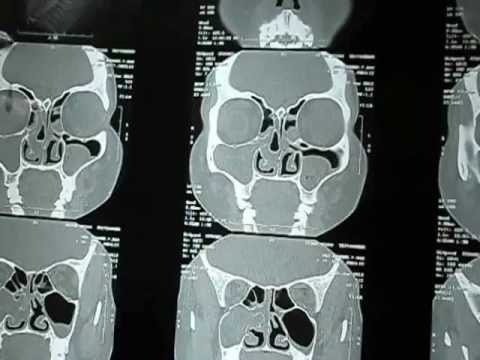

Pre Op Evaluation of Sinus Surgery.AVI.

Pre op evaluation of CT images before the sinus surgery in Jubilee Hospital Trivandrum, South India